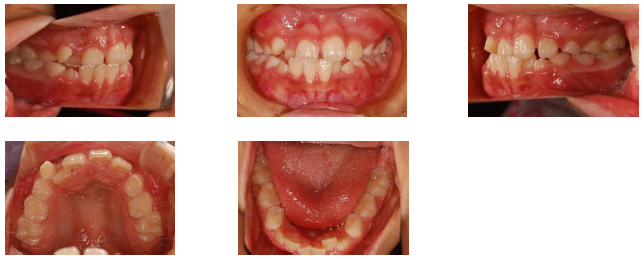

今日は、実際に治療をしている症例をご紹介します。小さい頃から咬み合わせが逆でしたが、そのうち治るかと様子見をしていたものの、大人の歯が生えてきても治らなかったので相談にいらした小学校低学年の患者さんです。

検査の結果、上下の顎が狭いので今後大人の歯が並ぶ場所が足りないことと、上の歯が内側から生えてきていたことが分かりました。また、上と下の歯の中心がずれていることが分かるかと思います。これを放置すると顔が曲がって成長してしまうため、早めに受け口を治して正しく成長できるようにすることとなりました。